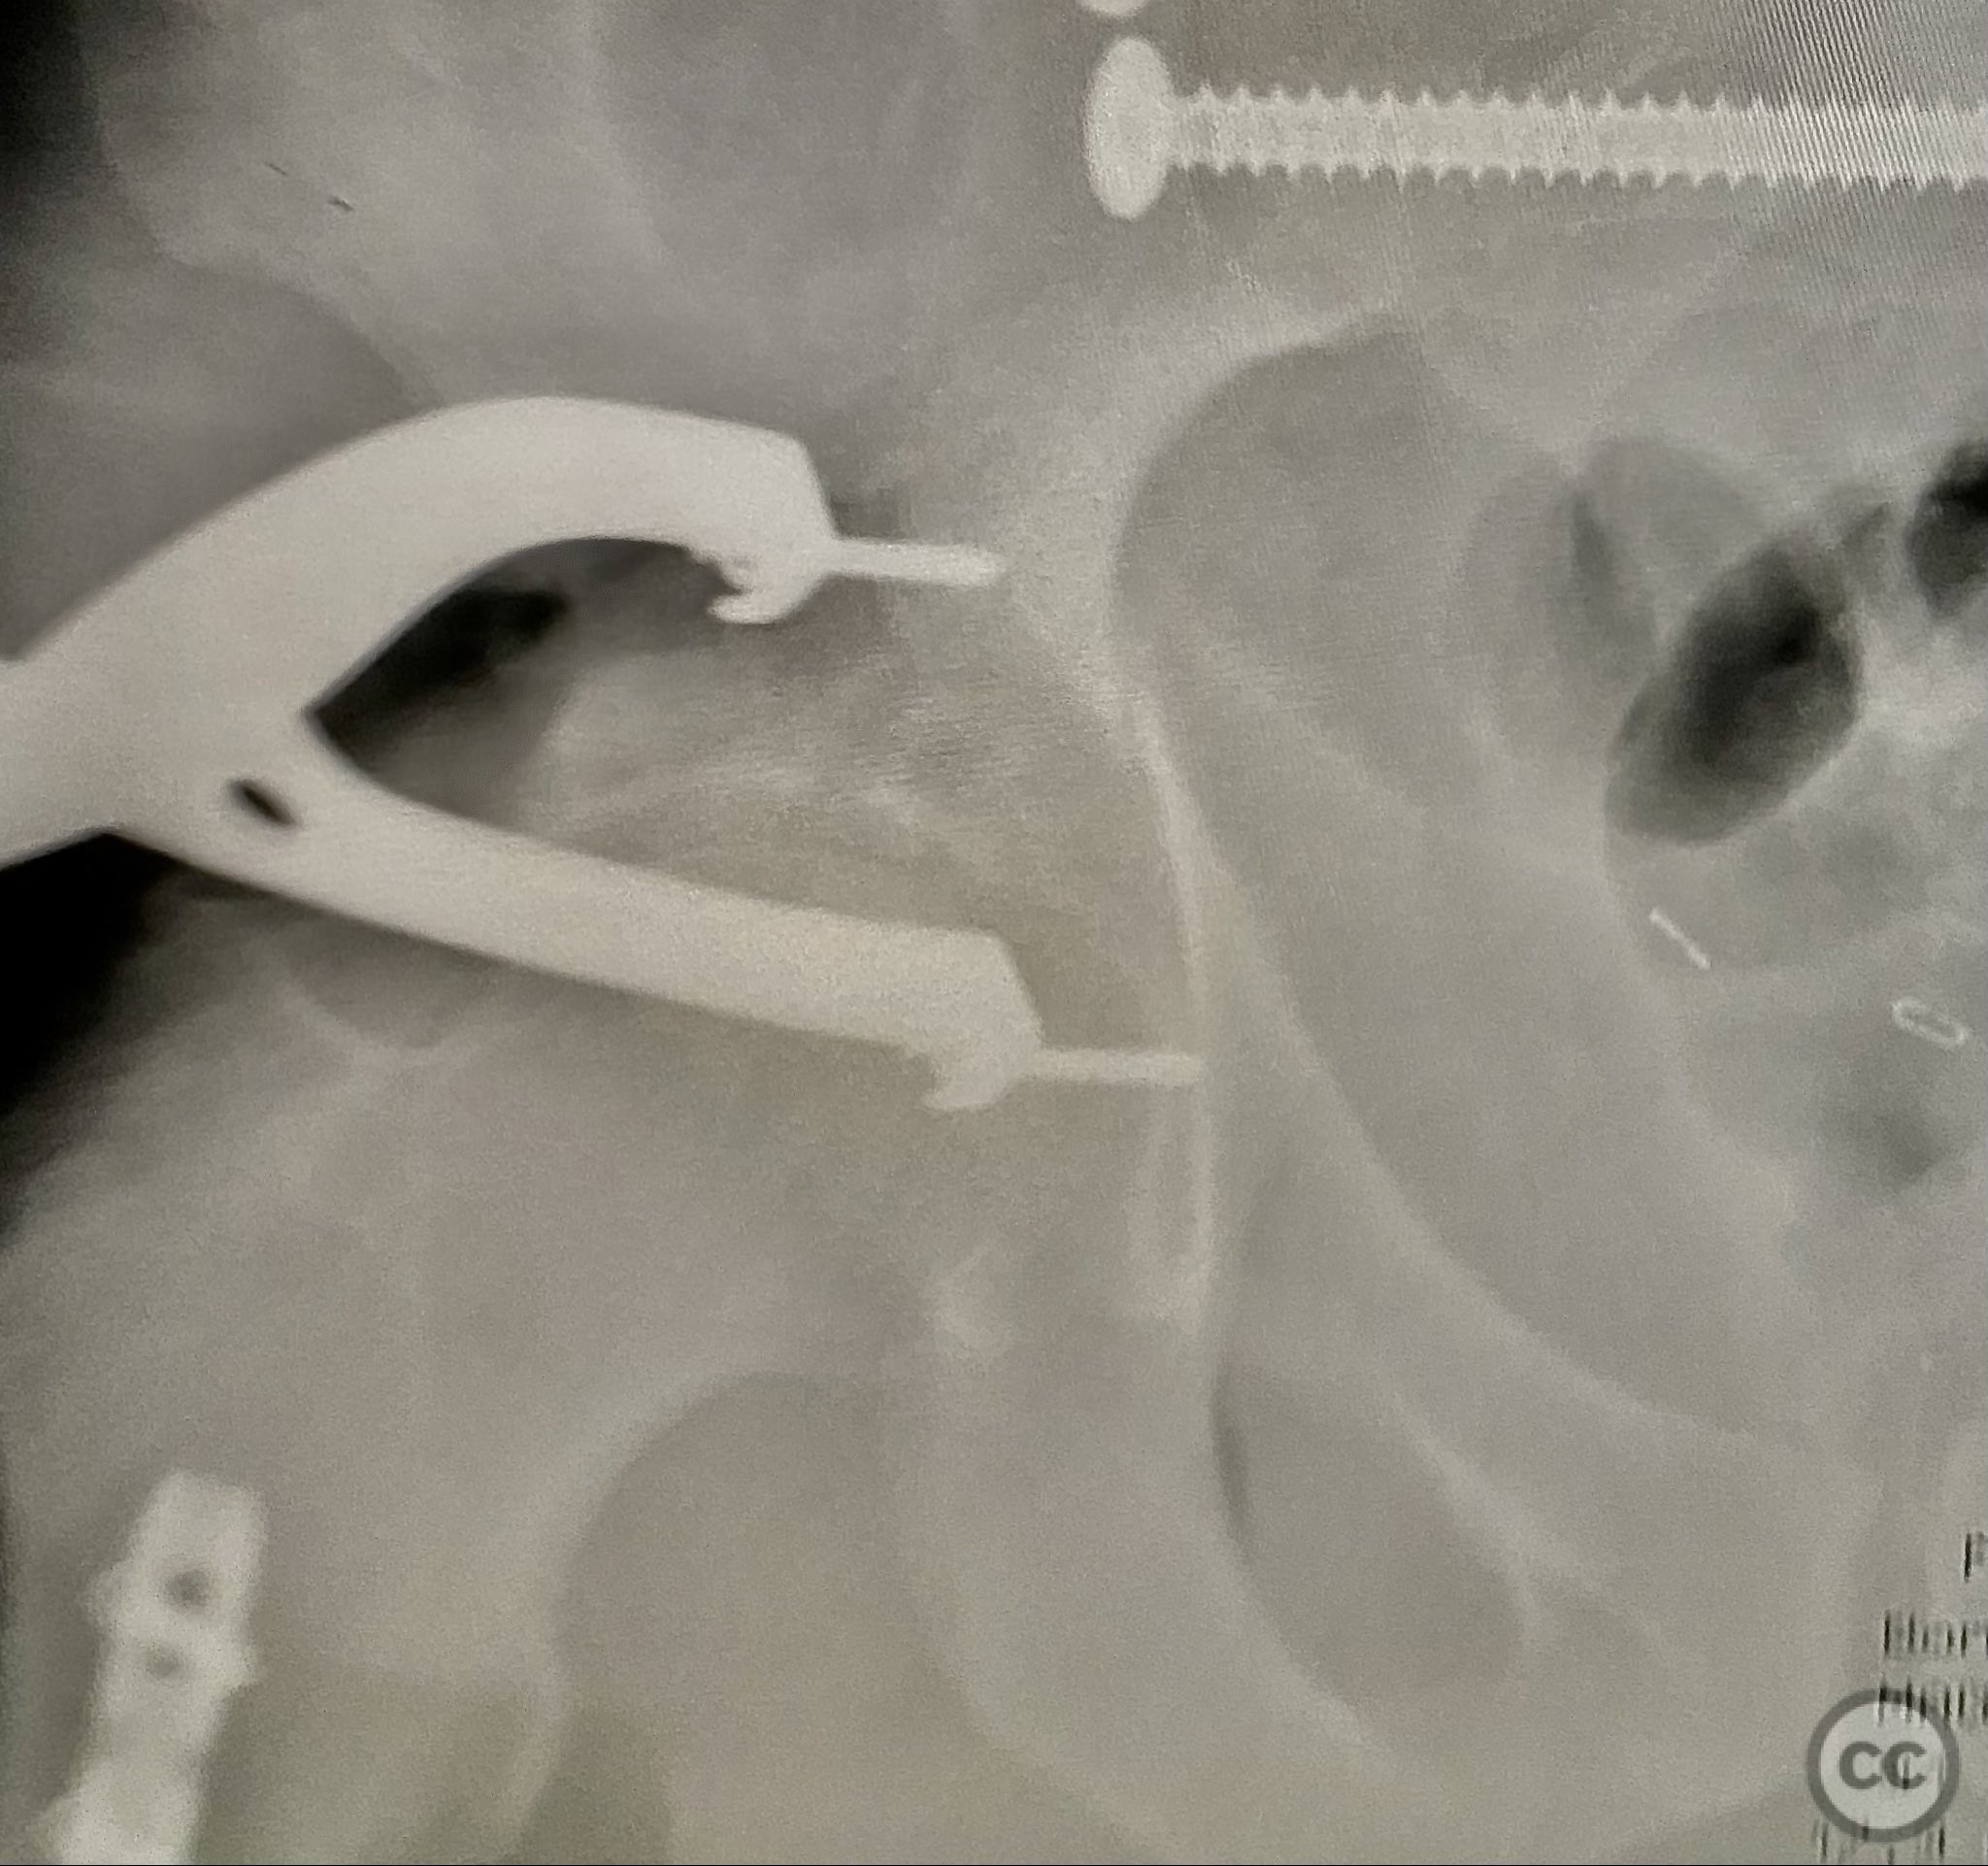

Operative remarks:

Initial reduction of the posterior column was attempted using a Jungbluth clamp; however, intraoperative fluoroscopy revealed suboptimal reduction despite satisfactory direct visualization. A perpendicular reduction clamp was then applied, resulting in improved alignment as confirmed by fluoroscopy. The transverse acetabular fracture was stabilized with two 4.5 mm cortical screws placed across the fracture line, followed by application of posterior column plates for additional stability. The symphyseal disruption was managed non-operatively without direct stabilization.